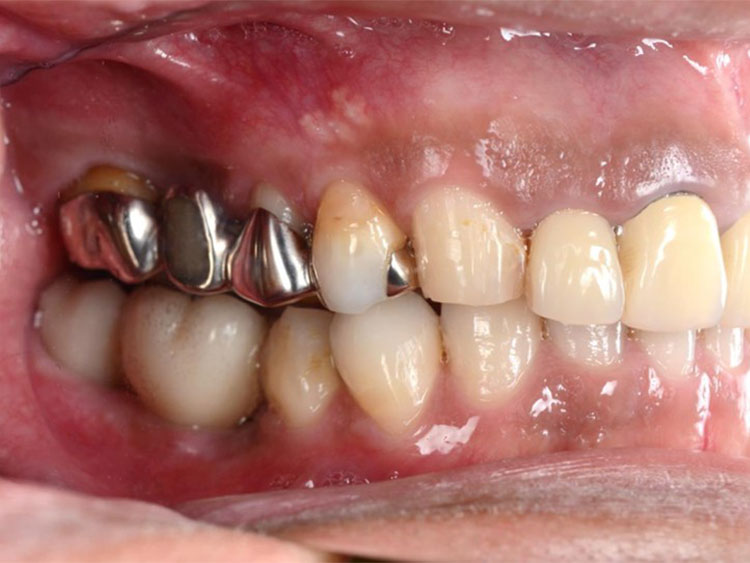

All-on-4症例 Case1

Treatment cases

Before

After

インプラント治療は、咀嚼機能の改善だけでなく、 口腔周囲筋の発達により見た目の若返りにも貢献してくれます。